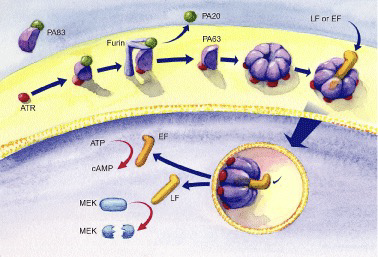

Bacillus anthracis (炭疽桿菌, G+)

- 3 proteins

- Protective Antigen(PA83): B toxin

- Edema factor : 水腫, A toxin

- Lethal factor :致命,殺細胞,A toxin

- 2 exotoxin

- Edema toxin = PA63+EF

- Lethal toxin = PA63+LF

Tip

- EF → cAMP

- cAMP 在腸道導致腹瀉

- EF → cAMP

- cAMP 在腸道導致腹瀉